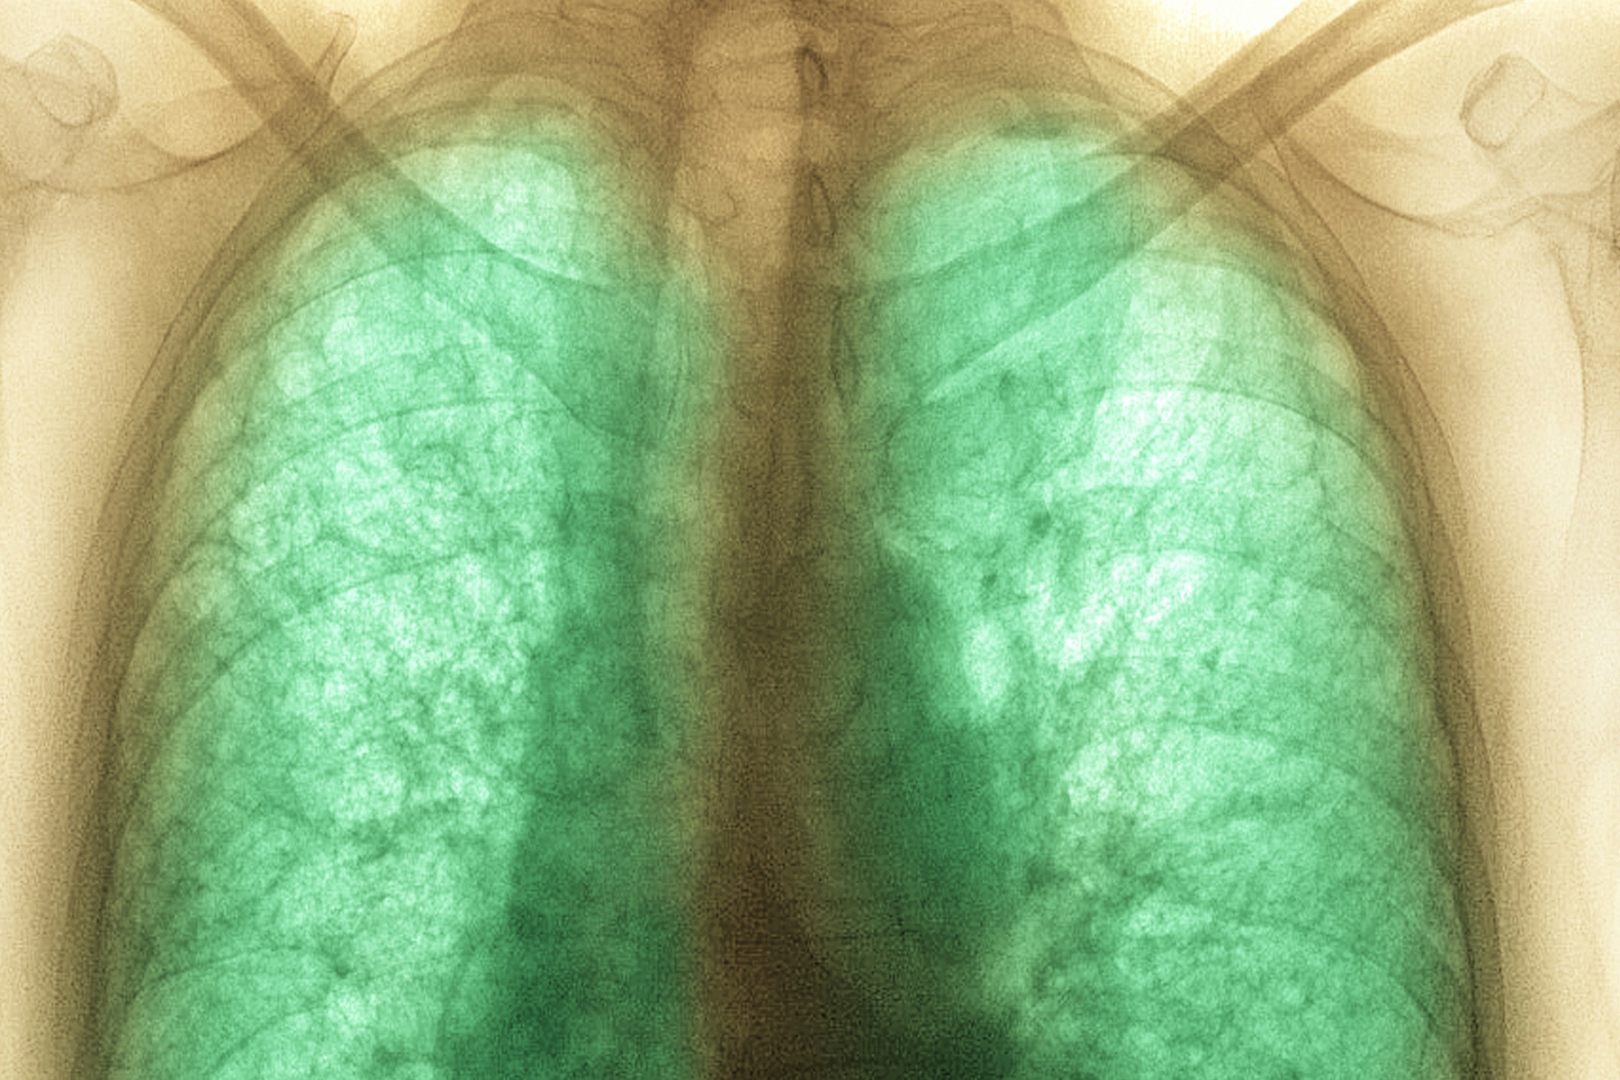

В следующей фазе заболевания COVID-19 инфекция обычно продвигается в легкие, что может вызвать пневмонию и затруднение дыхания. Ухудшение здоровья с высокой температурой тела является источником обеспокоенности и тревоги. Это может повредить иммунную систему, потому что организм борется с вирусом, но при этом ищет силы, чтобы справиться со стрессом.

В тяжелых случаях заболевания COVID-19 пациентам требуется госпитализация в отделение реанимации. Эти симптомы включают:

недостаток кислорода;

сильная бессонница;

потеря сознания;

затрудненное дыхание;

нарушение работы печени и почек.

Тщательный медицинский уход, включая использование кислорода и механической вентиляции легких являются необходимыми для лечения тяжелых случаев COVID-19.